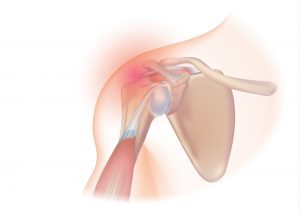

The rotator cuff is a group of 4 tendons (tendons are the connection of muscles to bone) that connect to the head of the humerus (the ball of the ball and socket joint of the shoulder). It is made up of the subscapularis, the supraspinatus, the infraspinatus and the teres minor. These muscles are responsible for many of the motions of the shoulder. The large muscle that is more superficial than these muscles is the deltoid muscle. The shoulder joint proper is made up of the head of the humerus and the glenoid which is the socket and is actually a part of the scapula or wing bone. The glenoid is circumferentially lined by a thick fibrous ligament called the labrum. The clavicle (collar bone) joins the roof of the shoulder, the acromium (which is also part of the scapula), to form the acromioclavicular (ac) joint.

The rotator cuff muscles are relatively small and can be injured by an acute stress that exceeds their tolerance. Degeneration of the rotator cuff tendon also occurs from chronic use when the body’s rate of tissue damage exceeds the rate of repair. This is a normal part of the ‘maturing’ process. To conceptualize this process, think of a rope rubbing back and forth over a rock. It gradually becomes thinner (partial thickness tear) and eventually may tear all the way through (full thickness tear). The rotator cuff is a wide tendon so one may have a partial or full thickness tear through part of the tendon but not the entire tendon. In the population at large about 25% of people age 40-60 years old have partial thickness rotator cuff tears. By age 60, 20%+ of the population has a full thickness tear (all the way through a portion of the tendon) and by age 80 over half the population has a full thickness tear. There are many people with a full thickness tear that have minimal or no symptoms and don’t know they have a rotator cuff tear. As we age, the thickness, elasticity and quality of the tendon tissues deteriorate. The labrum also wears over time and a very large percentage of patients over 40 have some tearing of the labrum and most do not have any awareness of this phenomenon. There are secondary changes that occur in the shoulder concurrent with rotator cuff degeneration including bone spurs of the acromion and the ac joint. The obvious question is that if so many people have rotator cuff tears why do some have pain and dysfunction and others do not. This is not well established but there are many theories about this that have do to with the geometry of the tear, the basic anatomy of the individual and the stresses that are placed on the shoulder and the vascularity of the tendon. It is also why, even with a full thickness tear, sometimes the right treatment is not surgical repair but the presence of pain is often an indicator that in the long term surgical treatment will be more successful. Recent studies have clearly shown that patients with full thickness tears who chose surgery had better long term results in terms of function and pain relief than those who did not have a surgical repair. Also, most labral tears do not have to be treated surgically although there are some that require it.